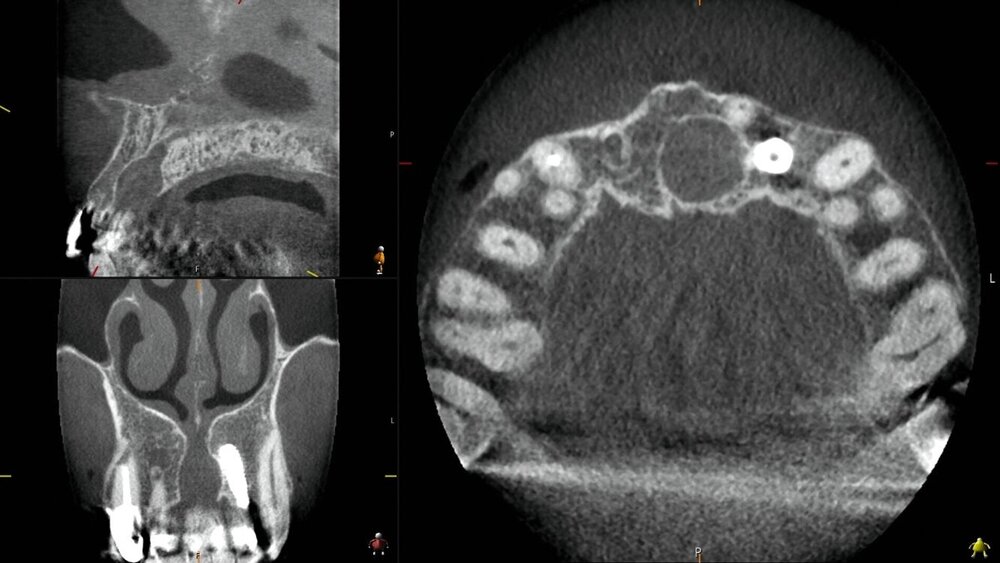

In der angefertigten Digitalen Volumentomografie konnte eine im Durchmesser circa 8 mm große Erweiterung des Canalis incisivus gemessen werden (Abbildung 1). Bei typischem Erscheinungsbild einer infizierten nasopalatinalen Zyste wurde die Indikation zur Entfernung derselben gestellt. Präoperativ über Rezidiv und Gefühlsstörung des anterioren Gaumens aufgeklärt, willigte der Patient in die Operation in Lokalanästhesie ein.